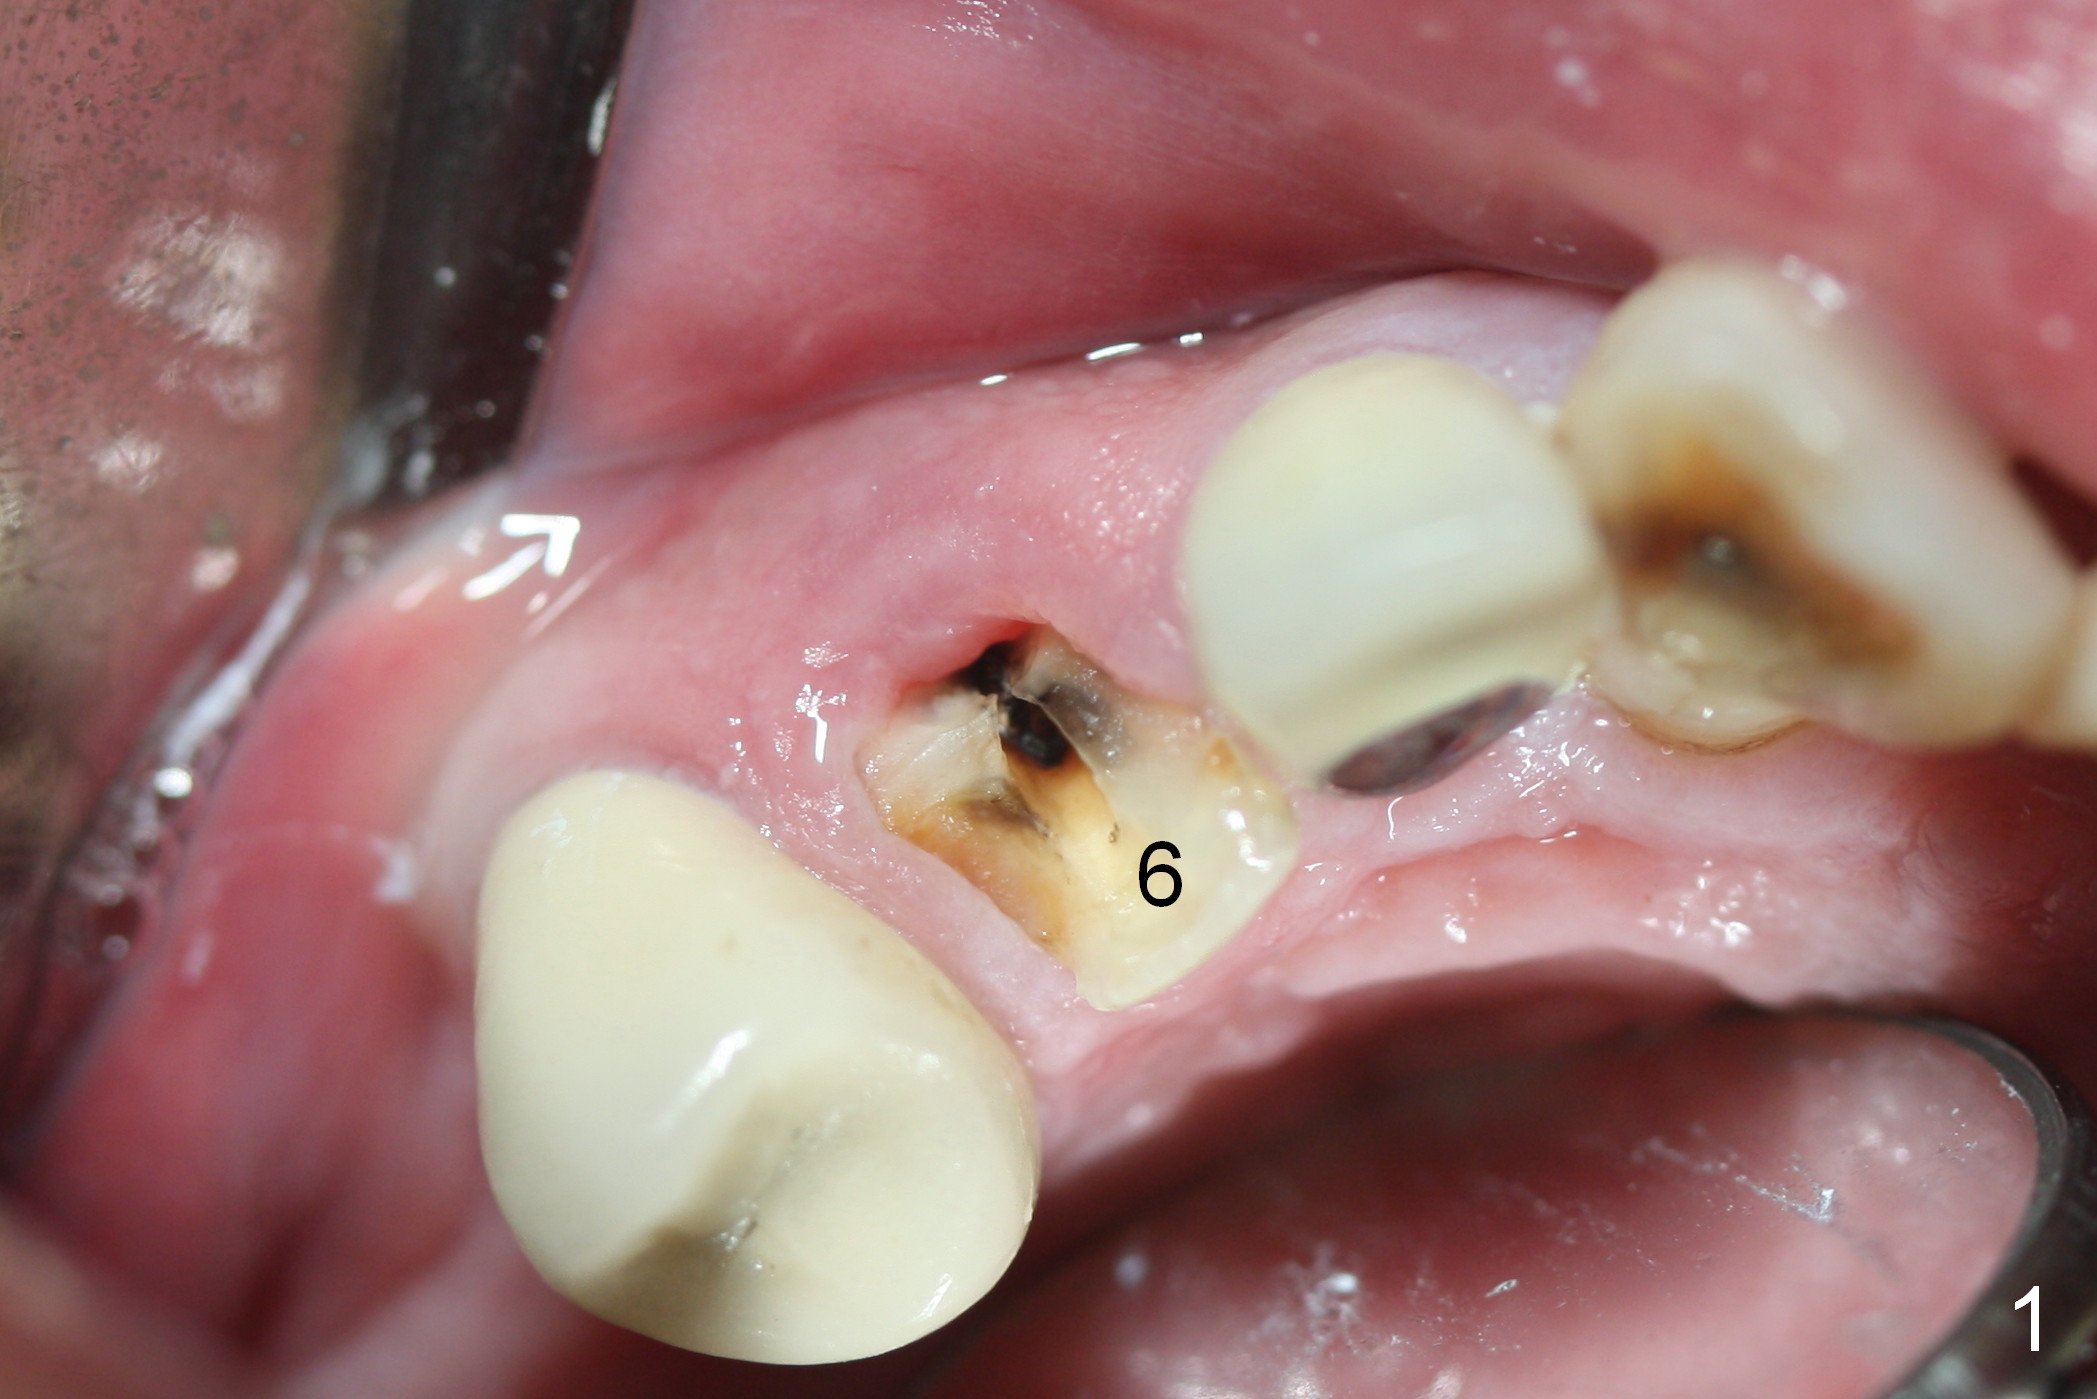

After extraction of the subgingival fractured upper right canine (Fig.1), the buccal plate is found to have been perforated at the apex. the root is measured 5x12 mm. Initial osteotomy with a 2 mm pilot drill shows that the bone is soft (Fig.2). After use of a 3.2 mm drill (underprep, normal drill size (3.7 mm)), a 4.5x15 mm implant is placed with insertion torque > 50 Ncm (Fig.3). The implant is further torqued until the implant plateau is 3 mm apical to the buccal gingival margin; a 5.5x5(3) mm abutment is placed (Fig.4,5 A). Osteogen plug is inserted into the apex of the socket, while the rest of gap is filled with mineralized cortical allograft and Osteogen. An immediate provisional (Fig.5,6 P) is fabricated to keep the graft in place, followed by periodontal dressing (Fig.6).

Three months postop, the provisional is dislodged (Fig.7-9). The mesial gingiva is hypertrophic buccally (Fig.8 *) and lingually (Fig.9 *). There appears to biologic width violation (Fig.5). The abutment should be changed to the one with smaller in diameter and longer in cuff (4.5x5(4) mm) with the buccal margin reduction.